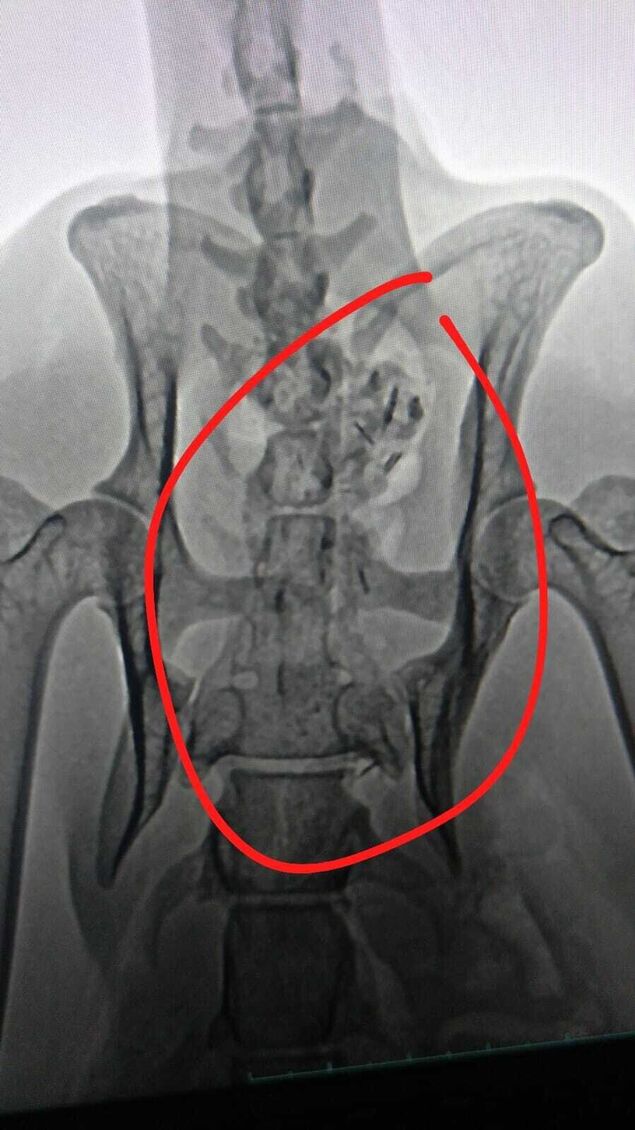

"Wenn wir das auf den Röntgenbildern nicht nachweisen könnten, glaubt uns das niemand", behauptet Birgit Block, Vorsitzende des Cuxhavener Tierheim-Vereins "Eine Pfote, ein Versprechen": "Es ist schier unglaublich, was dieser lieben Katze mitten in Cuxhaven widerfahren ist."

"Was bewegt Menschen, so etwas Grausames zu machen?", fragt Birgit Block empört. Denn eine aufgelesene Katze sei mit einer Schrotflinte angeschossen worden. Danach habe sich das Tier kaum bewegen können und auf seinen Tod gewartet. "In dieser Zeit des Wartens hat sie wahnsinnig abgebaut und sich ihr Sprunggelenk kaputt gelegen", berichtet die Tierschützerin.

Derzeit sei die Katze medikamentös abgedeckt. "Wir gucken, wie der Verlauf in den nächsten 14 Tagen ist. Von einer OP wird erst mal abgesehen, da es zu kompliziert wird", erklärt die Tierheim-Vereinsvorsitzende. Die Tierschützer würden sich freuen, "wenn wir einen Paten für diese zauberhafte Samtpfote finden könnten".